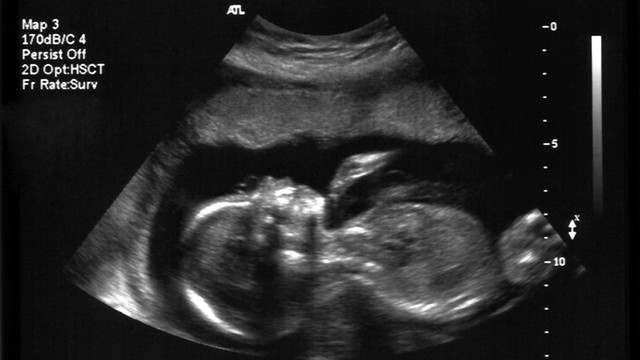

sinh sản